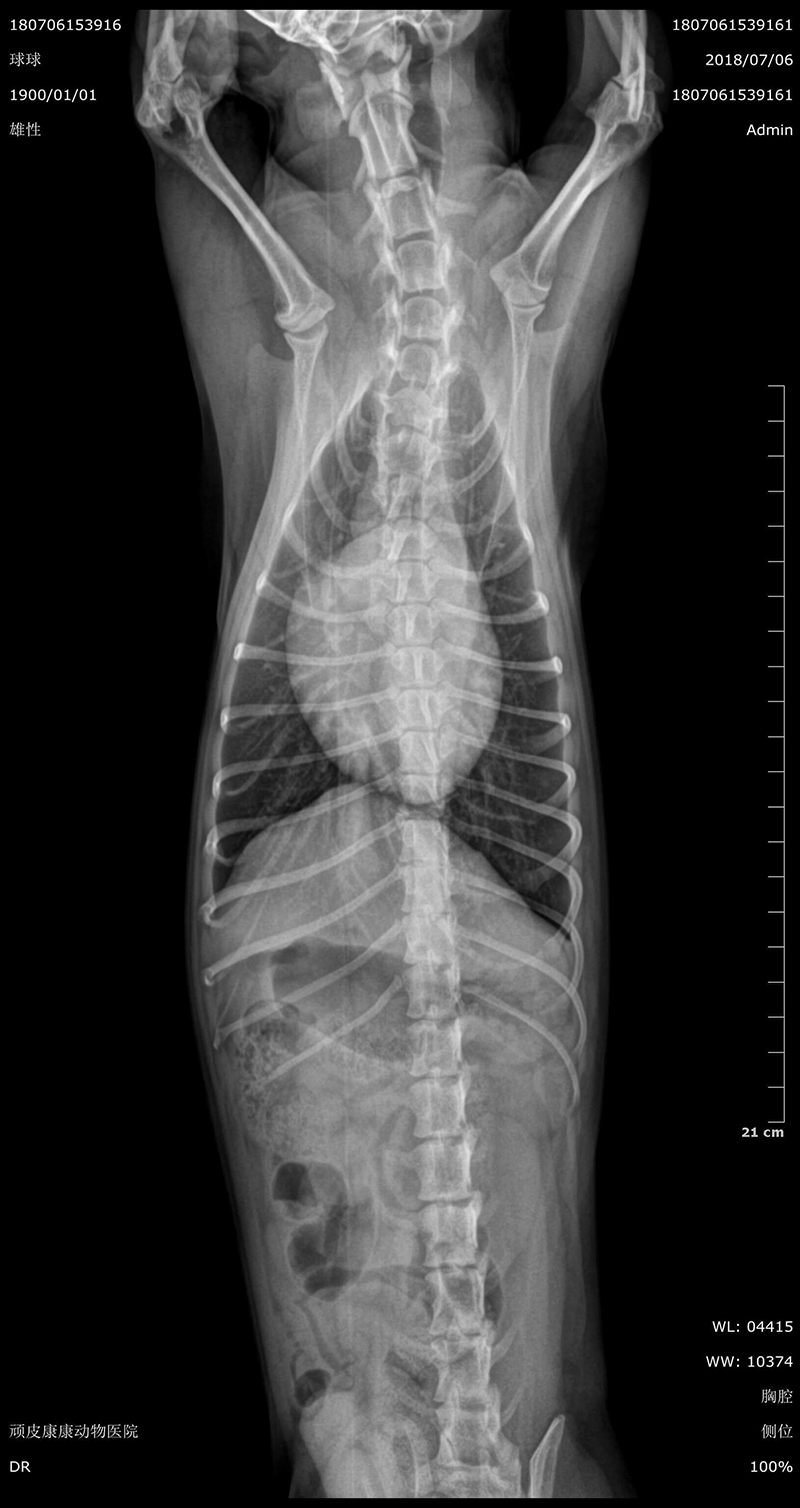

• Specification

• Clinical Image